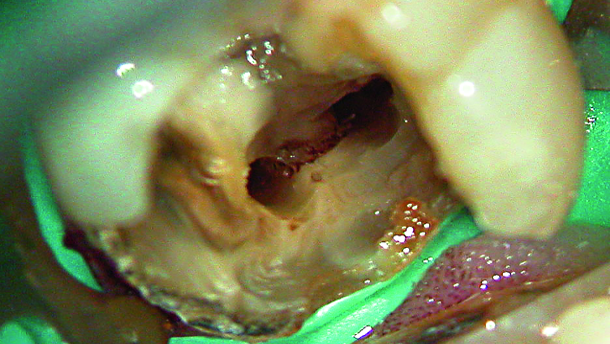

Current techniques are not always completely effective and it has been well recognised that while some part of the root canal are over prepared with rotary instrumentation, other surfaces are not touched. One study concluded that at least 35 % of the surface area of canals had remained untouched by rotary preparation (Peters et al., 2001). In another study the results were even worse, 60–80 % untreated surfaces were left in the distal canals of lower molars, with 65–75 % in the apical 4 mm after preparation (Paque et al., 2010). Oval canals are particularly challenging as the debris collects in the extensions and in isthmuses (Figs. 1a & b).

Fig. 1a: Debris left after root treatment of distal canal of a lower molar.

Fig. 1b: Radiograph of failed root canal treatment shown in Fig.1a.